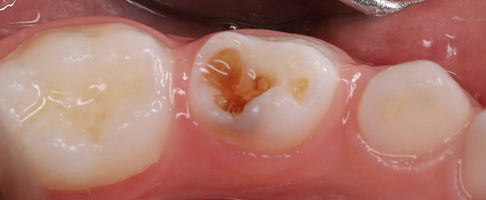

- лечение кариеса молочных зубов и его осложнений.

- лечение кариеса постоянных жевательных зубов.

В работе доктор применяет современные биосовместимые материалы, а также изоляционную систему коффердам. Ведет фотопротокол для контроля качества работы и наблюдения результатов лечения в динамике.